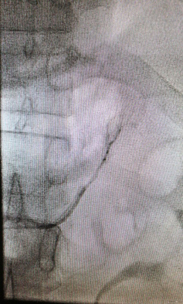

在征得患者及其家屬的同意后,我院多科協(xié)作行雙側(cè)腎上腺靜脈插管采血術(shù)。術(shù)中,僅僅在大腿根部局部皮膚麻醉,只需米粒大小一個針眼,通過股靜脈將導(dǎo)管通過很多道彎曲,分別送達(dá)左側(cè)和右側(cè)腎上腺靜脈。通過術(shù)中送檢血皮質(zhì)醇,證實雙側(cè)腎上腺靜脈插管成功。然后,手術(shù)醫(yī)生在雙側(cè)腎上腺靜脈和下腔靜脈同時取血。標(biāo)本送檢后,明確診斷為特發(fā)性醛固酮增多癥,左側(cè)腎上腺腺瘤無功能?;颊邿o需手術(shù),但需服用特殊的藥物控制血壓。在明確診斷后,心內(nèi)科立即為患者調(diào)整了降壓方案,針對特發(fā)性醛固酮增多癥進(jìn)行了針對性病因治療?;颊呒韧恢辈荒芸刂频难獕貉杆俚玫搅肆己每刂?。

左側(cè)腎上腺靜脈插管